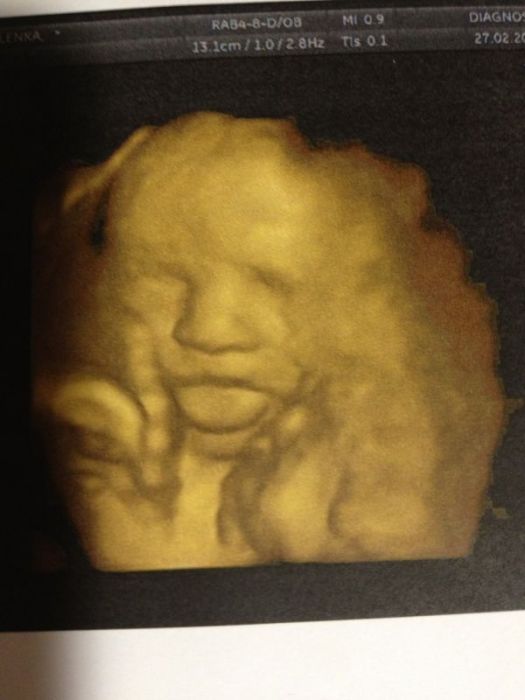

Tak posilam fotecky Manolita, na jedne ma vyplazlej jazyk, na druhe je videt jeho chlouba ( holky taky se Vam zda tak velka jako nam ;)???? ) a na jedne je vaznej.

Dik Zuzi, ale nepripada ti, ze ma takovej sirokej nosanek?? Ja mam nos malej a manzel taky, tak si tukame na celo po kom ten klukm je ;D???

já myslím Leni es., že ty nosánky to tgrochu zkresluje. Ségry malej taky má podobnou fotku z ult. a má jen takovej knoflíček.